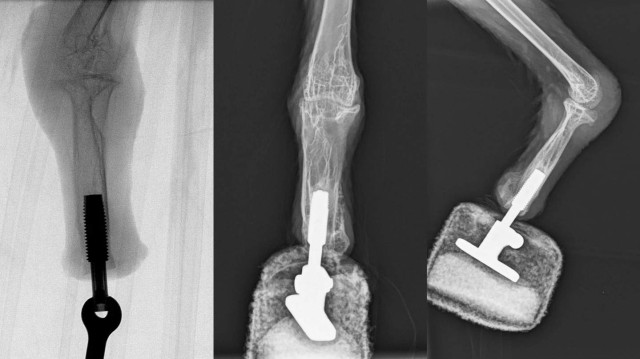

У випадку з бородатим грифом команда використовувала метод, відомий як остеоінтеграція. Сутність метода в тому, що основа штучної стопи приєднується безпосередньо до кінця кістки пошкодженої лапи.

Рентген лапи грифа з інтегрованим у кістку протезом